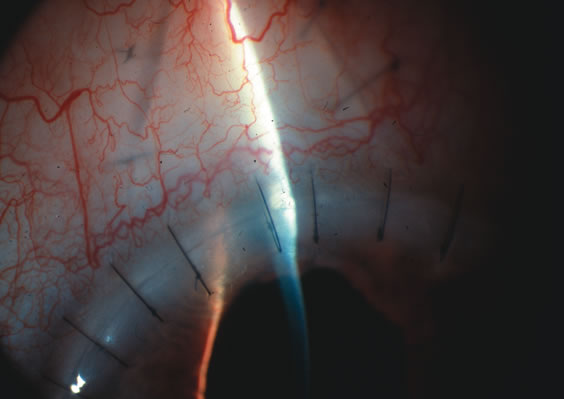

Fig. 4. Viscocanalostomy with deep sclerectomy and phacoemulsification. Nonpenetrating filtration procedures (NPFS) may be combined with phacoemulsification. Patients with mild disc damage and a history of limited topical drug therapy are the best candidates. Patients who require an IOP in the low teens are not good candidates for NPFS. By definition, NPFS is designed to lower IOP without penetrating into the anterior chamber, thereby avoiding the complications associated with trabeculectomy. Viscocanalostomy is intended to allow aqueous to percolate through a trabeculodescemetic membrane into a subscleral cavern created by the deep sclerectomy. The aqueous diffuses from the cavern into the dilated ostia of Schlemm's canal and into the episcleral venous plexus. A. Fashion a uniform 300-micron superficial scleral flap 1 mm into clear cornea. B. Construct a second 600-micron deep flap that facilitates the unroofing of Schlemm's canal, seen as the darker area. C. Use viscoelastic to dilate the ostia of Schlemm's canal. The major problem with viscocanalostomy is the eventual closure of the ostium decreasing flow to the episcleral plexus. D. Dissect the deep flap anteriorly into clear cornea creating the trabeculodescemetic membrane. This membrane is clearly seen between the scleral spur and the bend of the deep flap. The integrity of this membrane ensures the nonpenetrating portion of the surgery. Another problem with NPFS is the eventual fibrosis of this initially transparent membrane requiring goniopuncture. E. Deep sclerectomy gets its name from removal of the deep flap. Removal of this flap creates the potential subscleral space for accumulation of aqueous before it enters Schlemm's canal and exits the episcleral venous plexus. After removal of the deep flap, the superficial flap is sutured into place and conjunctiva closed. Approximately half of these procedures develop a shallow bleb.

Nonpenetrating procedures as they exist today generally decrease postoperative complications but do not reduce IOP as successfully as trabeculectomy.140 The success rate also appears to be highly dependent on race, length of topical antiglaucoma therapy, and prior ocular surgery.141,142 Deep sclerectomy combined with phacoemulsification results in an IOP reduction similar to phacotrabeculectomy at one year with comparable visual outcome.143 Phacoviscocanalostomy lowers IOP by approximately 33%144 through either a one- or two-site approach145 (Fig. 4). Nonpenetrating procedures are in evolution, and their place in long-term glaucoma care is still unclear.